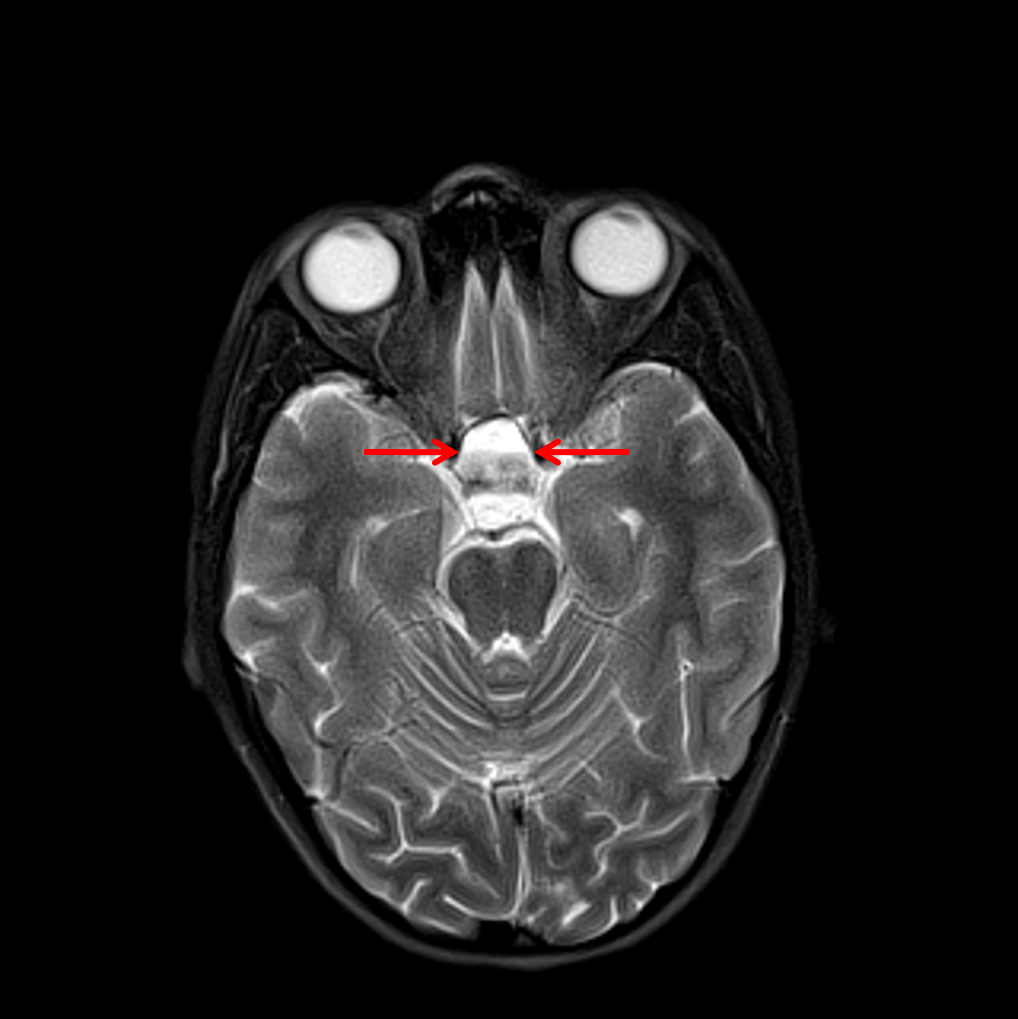

Three typical images of pituitary adenoma apoplexy. A Sagittal T1

Three typical images of pituitary adenoma apoplexy. A Sagittal T1 Fluid Fluid Level Pituitary a fluid level within a fluid cavity in pituitary tumors is rarely reported but is not uncommon in large/giant tumors. according to the fourth edition of the world health organization classification of endocrine tumors, published in 2017, cellular lineage and immunohistochemical stains for pituitary hormones and/or transcription factors help with making the correct pathologic diagnosis. Fluid Fluid Level Pituitary.